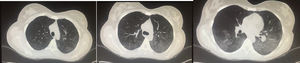

Diagnóstico. Entre los diferenciales se incluyen dolor musculoesquelético, embolismo pulmonar, infección, falla cardiaca, uremia y neoplasia. El análisis del líquido pleural es la principal herramienta diagnóstica. Típicamente, se trata de un exudado con elevación discreta de leucocitos, predominio de mononucleares (también hay polimorfonucleares) y niveles de glucosa normales o ligeramente bajos. El diferencial principal es con artritis reumatoide (AR), caracterizado por mayor elevación de leucocitos y DHL así como glucosa baja2. El papel que tiene la detección de anticuerpos antinucleares (ANA) en líquido pleural para el diagnóstico de pleuritis lúpica es controversial. Dos estudios recientes17,18 han reportado ANA a títulos >1:160 con sensibilidad del 85 al 90% y especificidad del 80% para diagnóstico de pleuritis lúpica en pacientes con lupus, sin embargo, títulos elevados también pueden encontrarse en otras entidades. En la figura 1 se muestra evidencia de derrame pleural en paciente con lupus que refirió datos clínicos de afección pleural.

Mujer de 22 años con LEG de 3 años de evolución caracterizado por manifestaciones cutáneas y musculoesqueléticas. Acude por cuadro de un mes de evolución caracterizado por dolor de tipo pleurítico y disnea. La radiografía de tórax simple reveló imágenes radiopacas que obliteran ángulos costodiafragmáticos compatibles con derrame pleural el cual fue abordado y posteriormente atribuido a actividad de su enfermedad de base.